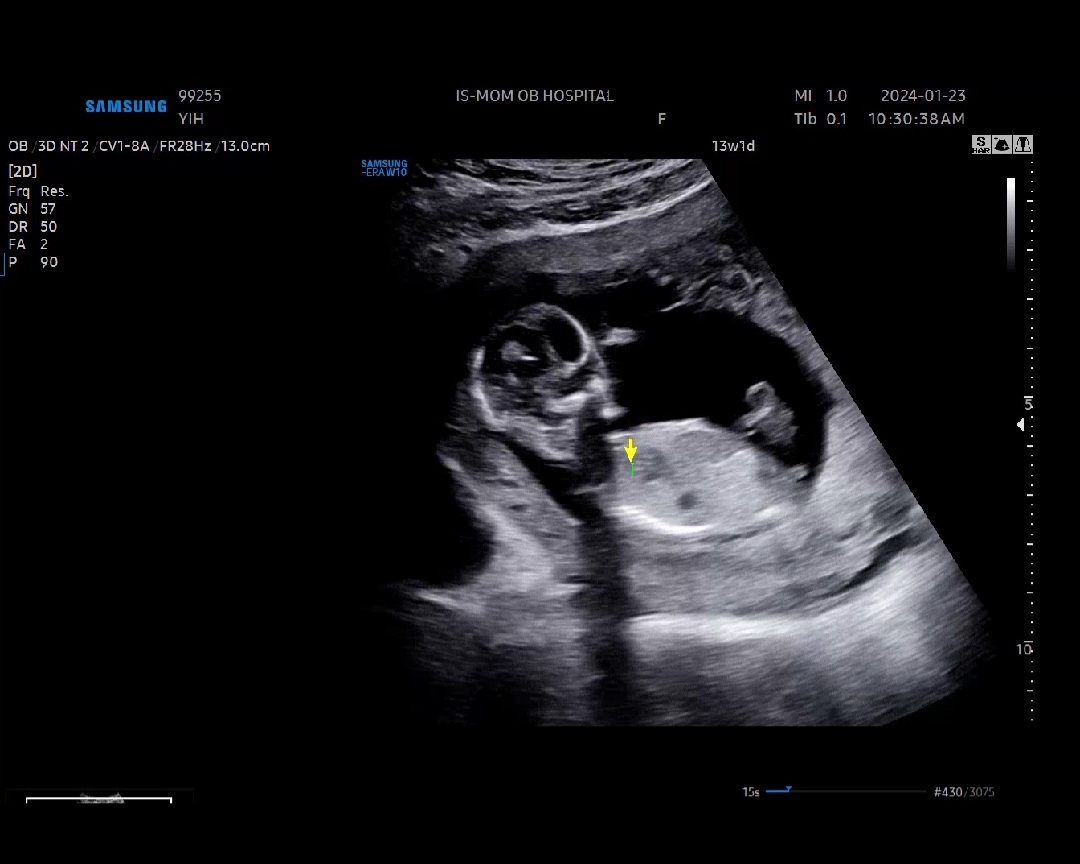

13주 1일차인데 아들일까요 딸일까요!!ㅠ

13주 1일차인데 혹시 각도법 잘 보시는 분 있나요..? 있으면 추측 한 번만 해주시면 감사드리겠습니당♡♡♡

아들인거같아요~~

아들 추측해봅니다 ㅋㅋㅋ